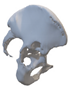

A 3D pelvis reconstruction allowed further processing using the Mimics Innovation Suite (Materialize NV, Leuven, Belgium), which is an engineering software package that enables 3D medical imaging and surgical-related planning. So, the design of the patient-specific aiming device was based on a 3D reconstruction of the patient’s own anatomy. After importing and transforming the two-dimensional Digital Imaging and Communications in Medicine (DICOM) standard file, the radiation absorption range was selected using the windowing method for spatial imaging of the reliable bone structure (Figure 1).

Figure 1.

3D images of the mask that appeared when the CT scans were threshold and the spatial model derived from it. The heads of the implanted screws are displayed in purple.

The default threshold window ranges from 200 to 2000 HU according to the Hounsfield scale, modified to consider the parameterization of the recordings and the specific density of the selected bones.

The selected range is immediately displayed on the screen so that the consequence of the change in the threshold values can be immediately evaluated on the CT slice images in the form of a colored highlight.

The mask obtained in this way contained only the real bone volume relevant to the task, in our case, the pelvis with significant bone defects and the femur on the same side.

After smoothing the mask to remove surface roughness due to the low resolution of the diagnostic imaging, the hemi-pelvis with significant bone defect was printed using a Stratasys F270 (Stratasys Ltd., Rehovot, Israel) fused deposition modeling (FDM) 3D printer. A square grip was attached at the sacrum in such a way that the model could be exposed on a stand and used as a reference to facilitate the spatial orientation in the OR.